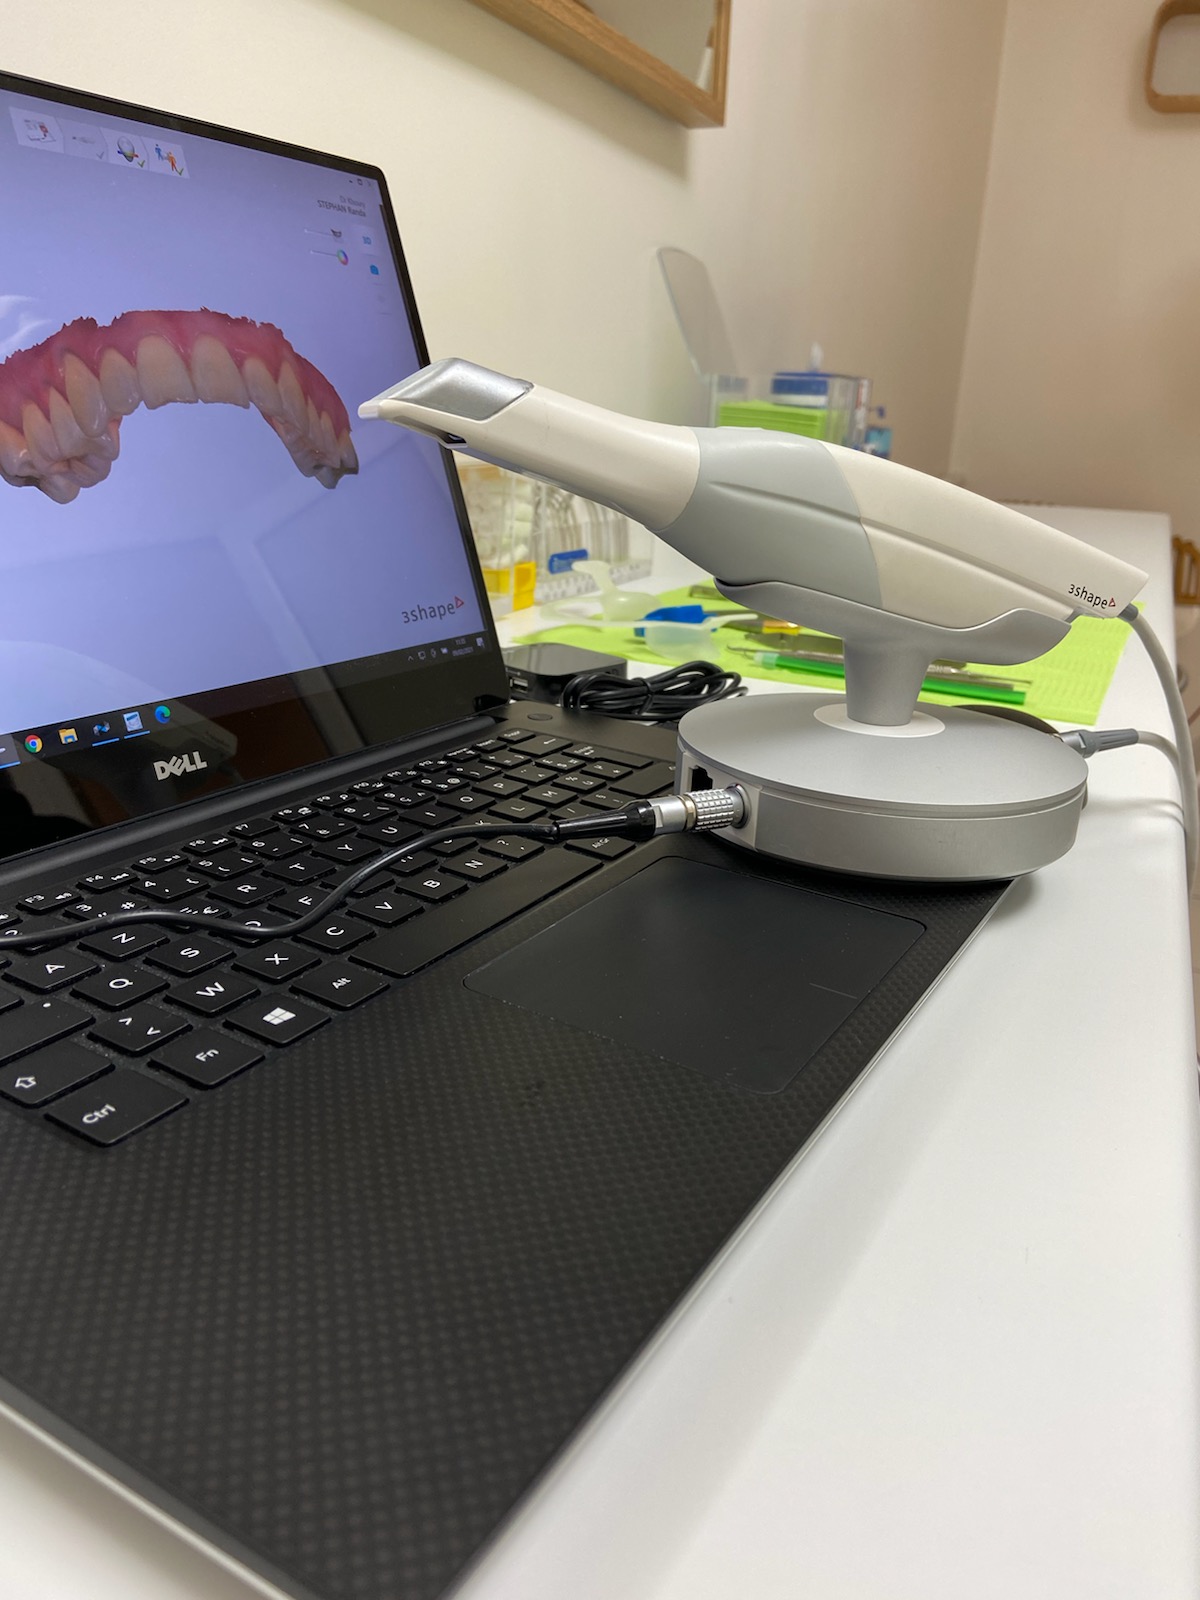

Nous mettons à votre disposition notre expérience des différents procédés orthodontiques actuels, qu’il s’agisse d'empreintes numérisées 3D, de radiographies numériques, d’orthodontie interceptive par appareillage fixe ou amovible, d’orthodontie vestibulaire avec des bagues (braces) métalliques, esthétiques ou transparentes, d’orthodontie linguale, ou d’orthodontie par gouttières transparentes ou par aligneurs, aligners (Invisalign®, Orthocaps®, Clear Aligner®).

Une prise d’empreintes dentaires sera réalisée numériquement par une caméra intra-orale, qui permet d'obtenir une image 3D des arcades dentaires, sans recours aux traditionnelles pâtes alginate ou silicone.